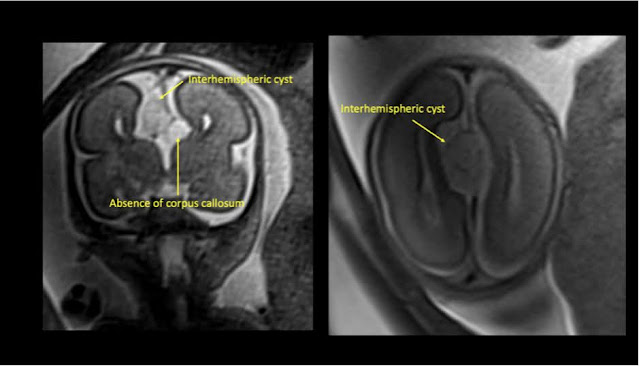

後續磁振造影確認個案的腦部胼胝體在影像上不可見、腦室擴張併 colpocephaly、interhemispheric cyst space 較明顯,且在較高的頂葉切面亦發現裂腦畸形(schizencephaly)(圖2),並應證雙側足內翻的狀況。

圖2:(個案一)磁振造影中,雙側側腦室擴張、胼胝體完全不可見及裂腦畸形(北榮放射線部提供)

在磁振造影的影像中確認個案的腦部胼胝體在影像上不可見、腦室呈現 colpocephaly,且interhemispheric cyst可見明顯囊壁,且靠近額葉的切面可觀察到cortical folding及cleft,無法排除是 schizencephaly 併有 polymicrogyria (圖4-5)。

圖4:(個案二)個案磁振造影腦部影像,沒有胼胝體,且 interhemispheric cyst有明顯的囊壁(北榮放射線部提供)